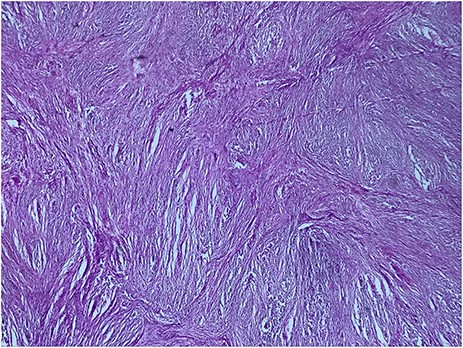

A 73-year-old woman was referred to our general surgery service. Her complain was intermittent gastric discomfort. There was no significant past medical history. There was no history of upper gastrointestinal bleed, or past surgical interventions with no abnormalities found on physical exam. An esophagogastroduodenoscopy (EGD) revealed a submucosal mass in the gastric body. Biopsy of the mass showed no evidence of malignancy. Computerized tomography (CT) scan of the abdomen showed an exophytic solid homogeneous mass along the greater curvature of the stomach and partly projected into the gastric lumen, causing smooth indentation measuring 8 × 8 × 6 cm3 (Fig. 1). The patient’s laboratory results were unremarkable. A presumptive diagnosis of GIST was made. The patient underwent successful wedge resection of the mass through laparotomy and the specimen was sent to pathology. On gross examination, a white intramural, nodular, solid mass measuring 8.7 × 8.8 × 6.7 cm was seen. A cut section revealed whirling trabeculation with a biphasic proliferation of compact hypercellular areas and myxoid hypocellular areas (Fig. 2). Sections from the tumor showed interlacing bundles of spindle cells, which had elongated nuclei, ill-defined cytoplasmic borders and palisading nuclei (Fig. 3). No nuclear atypia was noted. No mitotic activity and no necrosis were identified. There was no lymph node involvement and the surgical margin was negative for tumor cells. A histological diagnosis of a benign mesenchymal tumor was made. Immunohistochemistry (IHC) staining was strongly positive for S-100 (Fig. 4), whereas c-Kit, CD 34; DOG 1; smooth muscle actin (SMA), desmin and AE 1/AE 3 were negative. Hence, a final diagnosis of schwannoma was made. The postoperative period was uneventful and the patient was dismissed from the hospital after 5 days.

The tumor cells are narrow, elongated and wavy with tapered ends interspersed with collagen fibers (HE, G x 400)

A helpful histologic clue to the diagnosis of schwannoma is a peritumoral lymphoid cuff, which is rare in GIST [8]. Schwannoma cells have spindle-shaped nuclei and a fascicular arrangement. The diagnosis of schwannoma is based on immunohistochemical positivity for S-100 protein [1,8]. Our case was misdiagnosed as a GIST until these histological and immunohistochemical findings were revealed.